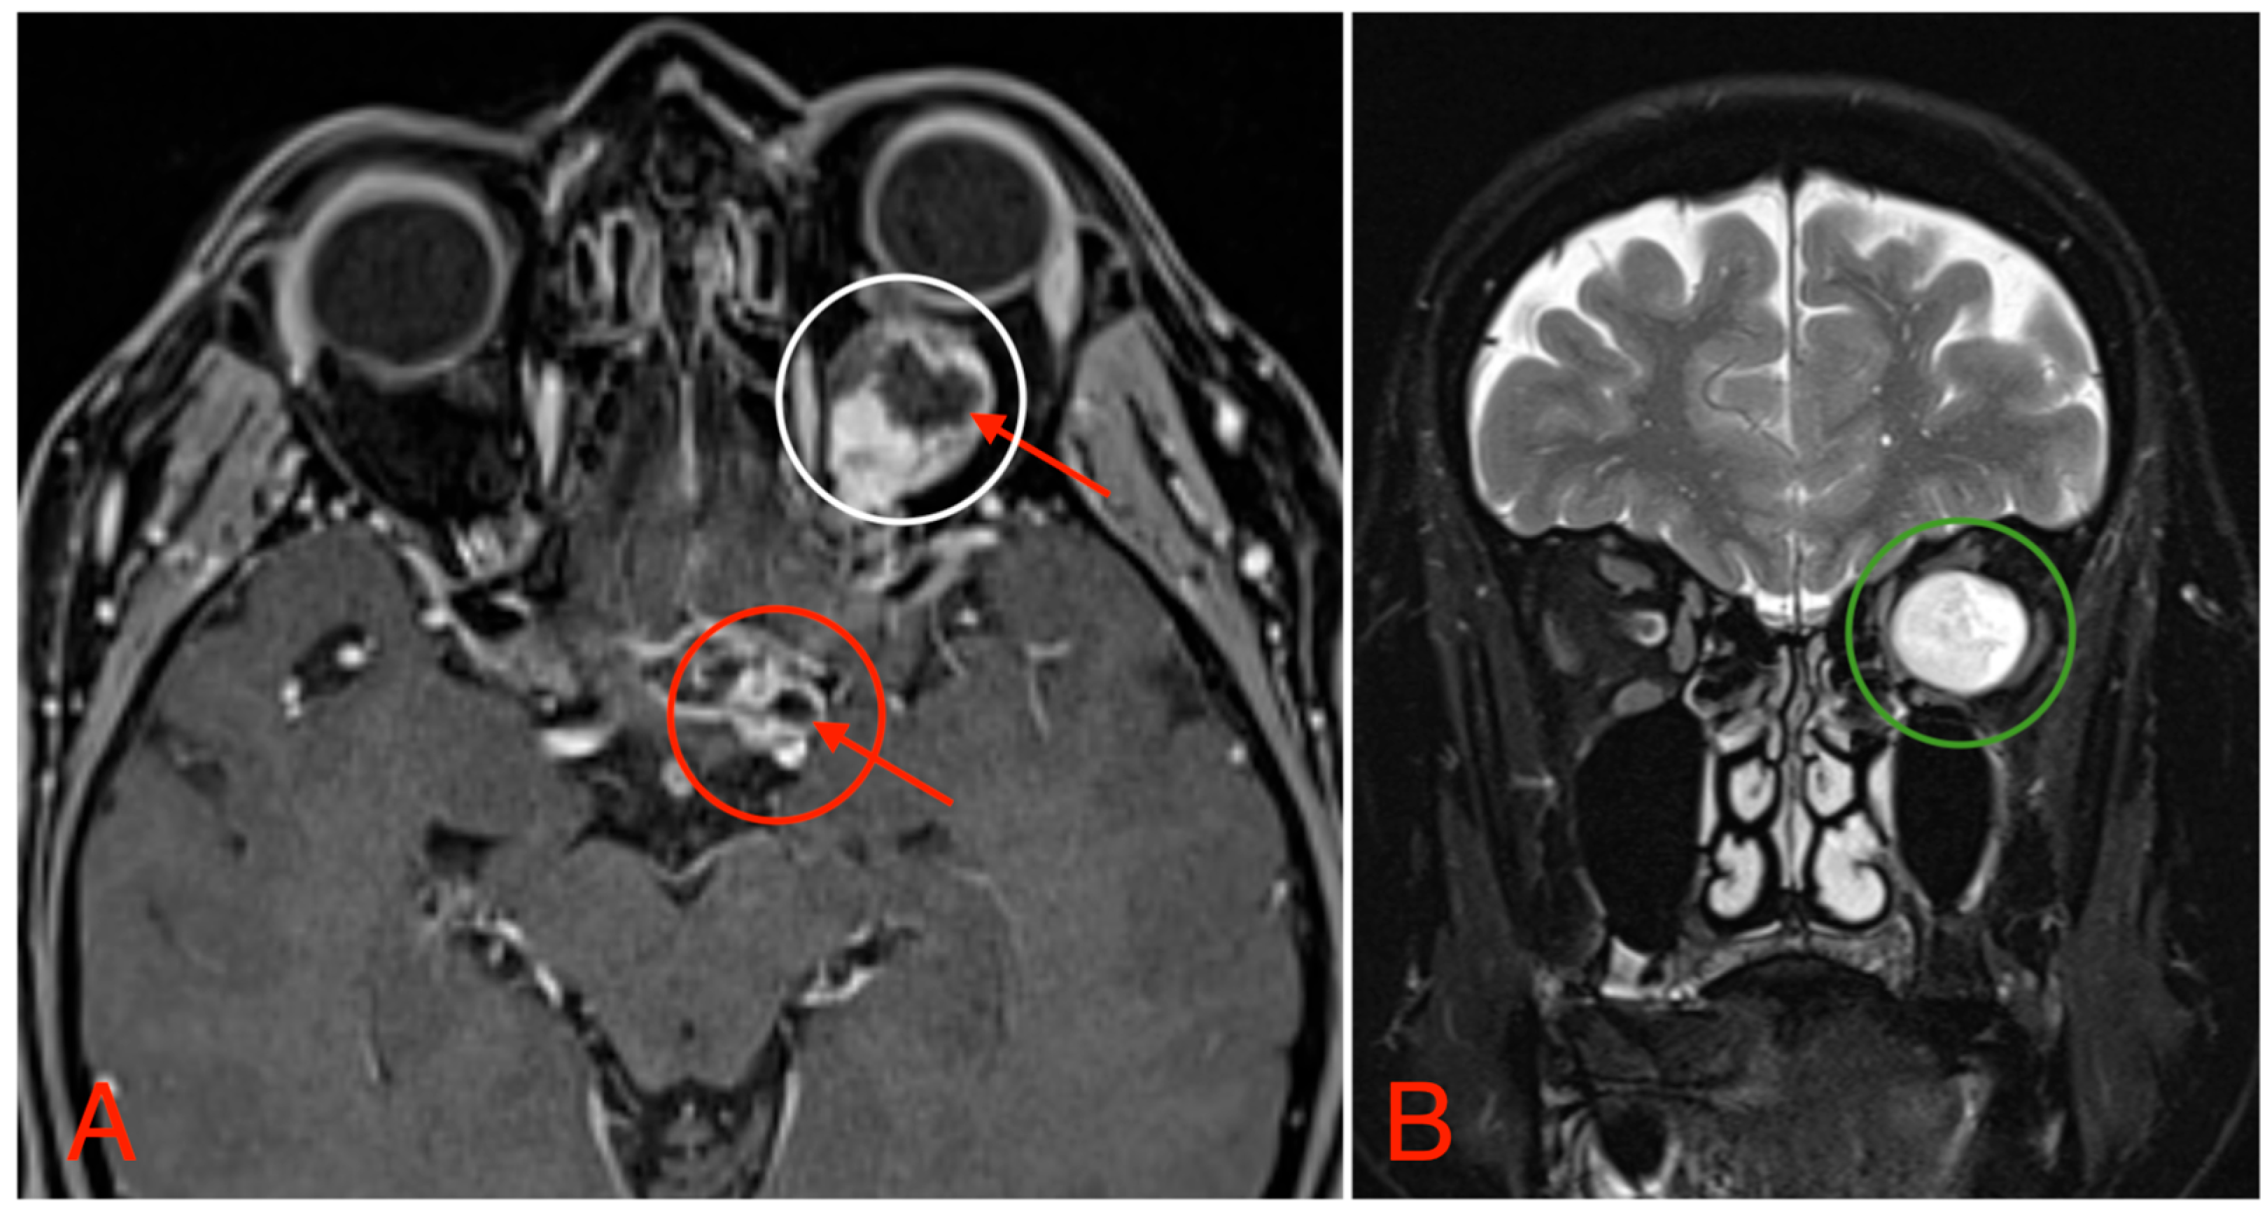

The CT scan revealed a pathological mass in the intraconal space, ~1.5 cm × 2.5 cm × 1.5 cm, which occupied most of the orbit. Noticeable thinning and depression of the rectus muscles of the eye were also noted (Figure 3). A cranial contrast enhanced MRI was conducted the following month, revealing an entirely altered optic nerve affecting the retrobulbar, prechiasmal, and optic chiasm level. A pathological, smoothly contoured mass with cystic changes was described and measured about 5.2 cm × 2.0 cm × 1.9 cm. Greater peripheral contrast accumulation in the pathological tissue extended along the optic chiasm and relatively close to the frontal lobe’s straight gyrus. The pathological mass also extended relatively close to the A1 segment of the anterior cerebral artery and stretched in the direction of the pituitary gland. A lateral depression of the extraocular muscles was also noted (Figure 4). The contrast-enhancing component of the tumor on diffusion-weighted imaging (DWI) sequence showed a restricted diffusion at an apparent diffusion coefficient (ADC) value of 1500 × 10−6 mm2/s, with a b value of 1000 s/mm2. A high T2 signal intensity was also noted.

Postoperative head MRI showed partial resection of the left optic nerve. Residual tumor tissue and edema were noted in the left retrobulbar space, extending into the left prechiasmal space and into the left side of the optic chiasm (Figure 8).

Figure 4. (A) MRI image, T1 VIBE fat-saturated post-gadolinium image sequence, axial plane, demonstrating an intraconal tumor which most likely originated from the optic nerve with intraconal and intracranial involvement, cystic changes (red arrows), and contrast enhancement (white circle). The intracranial compartment involves the optic chiasm with a mass effect on the surrounding structures and large blood vessels (red circle). (B) MRI image, T2 TSE Dixon sequence, coronal plane, showing both solid and cystic parts of the optic nerve tumor with a retrobulbar segment mass effect and extraocular muscle suppression (green circle).